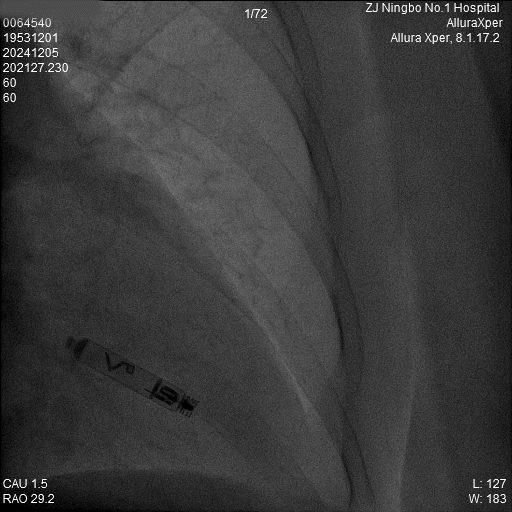

1.猪尾导管造影:软钢丝配合猪尾导管进入RV,造影显示RV轮廓。

a)RAO 30